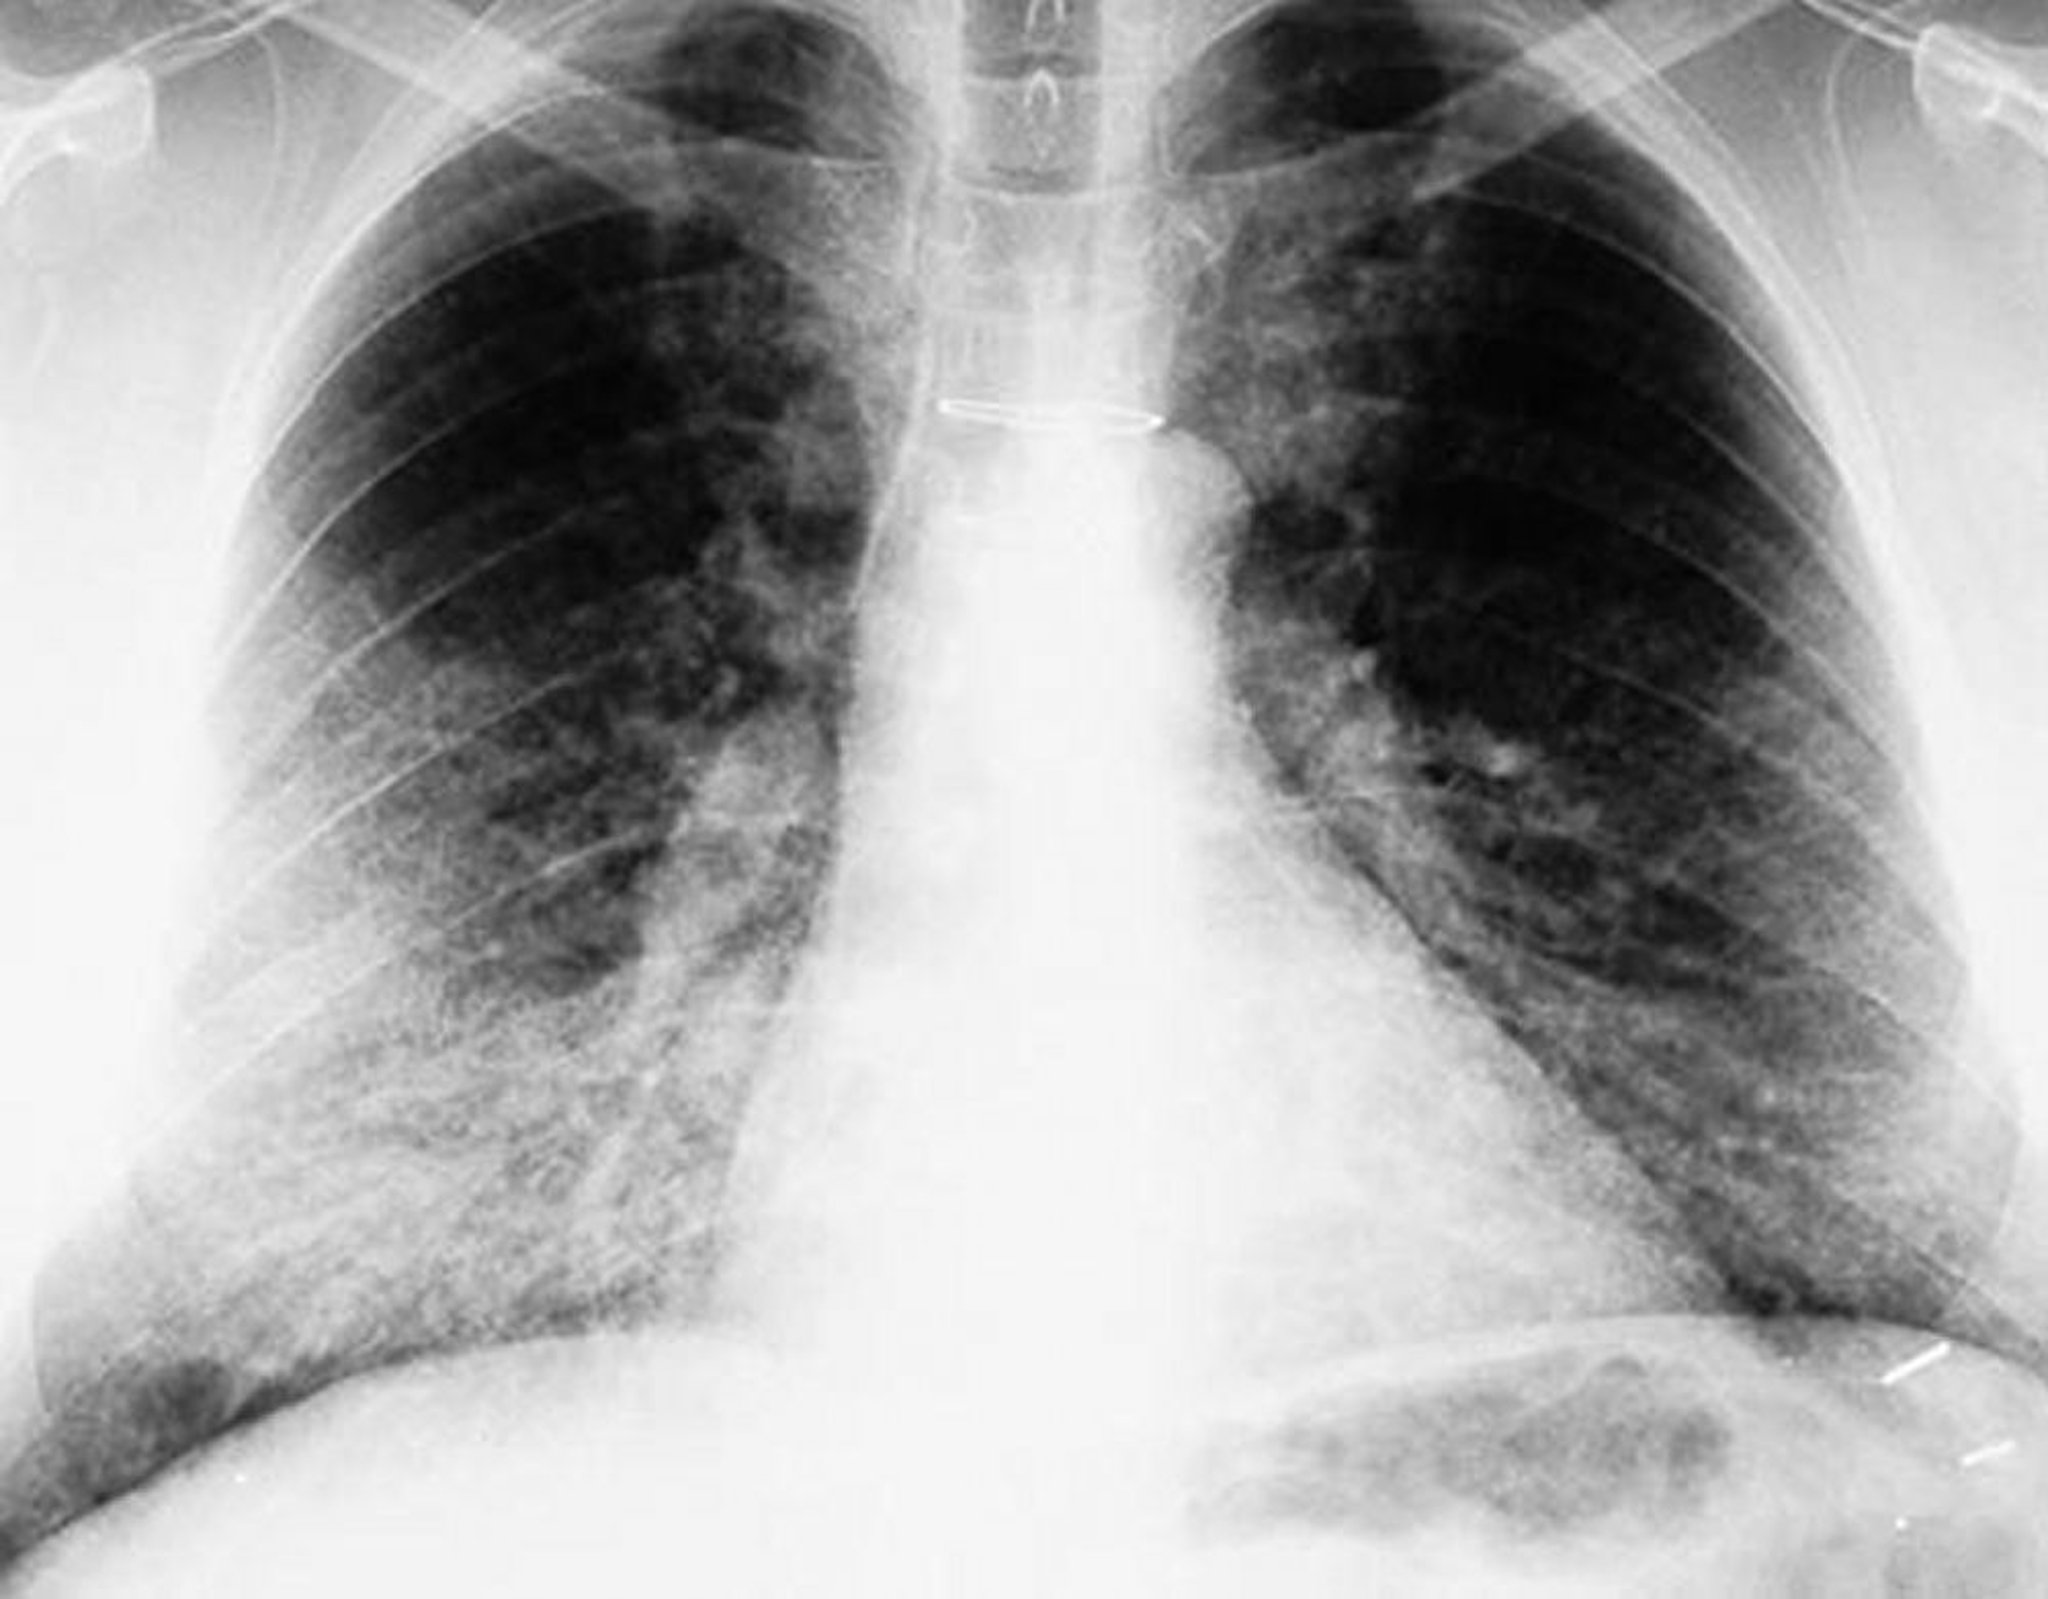

肺胞タンパク症(胸部X線)

胸部X線上で,両側性に肺底部優位の陰影がみられる。

By permission of the publisher.From Lynch III J, Myers J. In Bone's Atlas of Pulmonary and Critical Care Medicine.Edited by J Crapo.Philadelphia, Current Medicine, 2005.